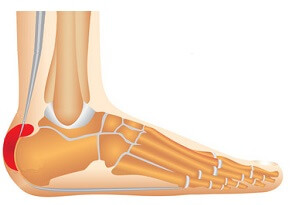

Bony growth on back of the heel which irritates surrounding structures aka Pump Bump

Causes: Rigid-backed shoes, high foot arches, calf tightness, genetics

Symptoms: Hard lump on back of heel, swelling, redness and pain around the achilles

Full Article: Haglund's Deformity